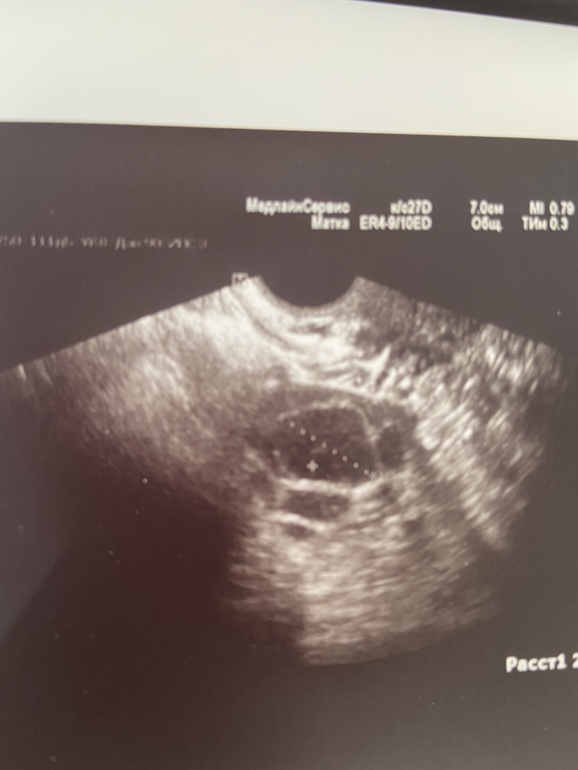

Еще обратите внимание на снимок матки если эндометрии светлый по сравнению с прошлым узи то овуляция была

и по эндометрию видно, что уже секреторного типа. А 8,1мм это хороший размер, главное чтобы качественный был.